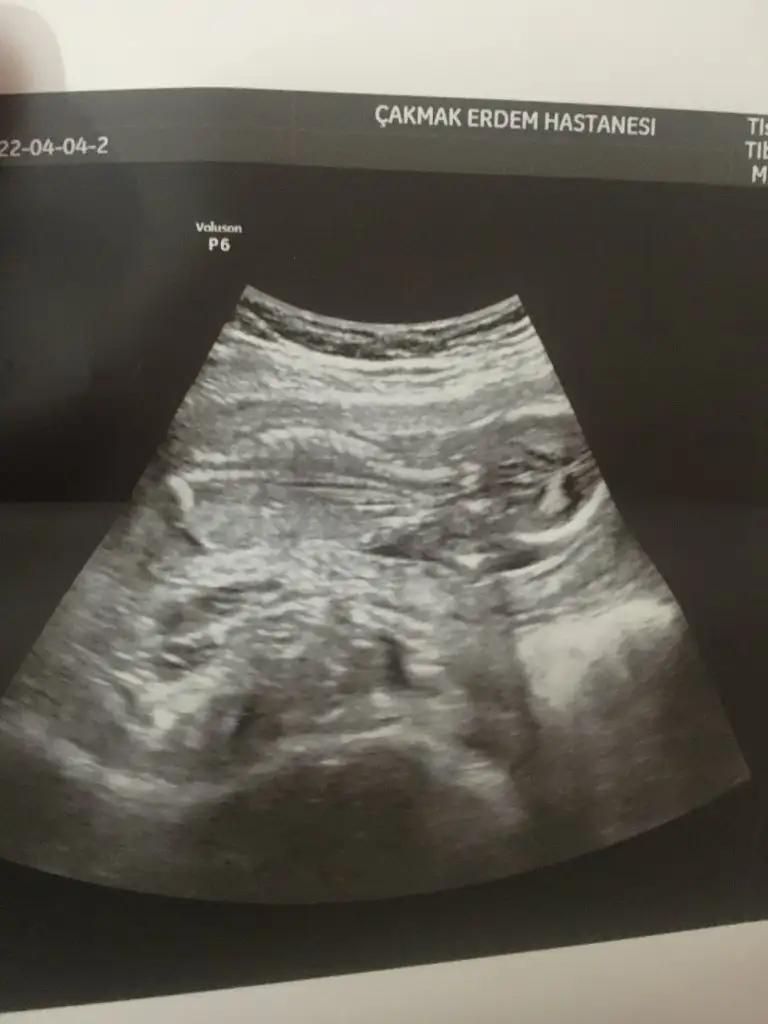

6+6 haftalık attım canım ikinci resimbebek göremedim yolk saç var canım maalesef yorum yapamam

vajina dan mı karından mı bakıldı?Düzenledim tekrar bakar mısınnPasha22

Vajinadanvajina dan mı karından mı bakıldı?

prenses gibi duruyor canımVajinadan![]()

kuzum bence kız, hayırlısı olsunBana da tahminde buluna bilir misiniz16 haftalık doktor erkek gibi dedi ama kordonda ola bilir dedi sizce nedir ?

Kuzum ben sana daha önce erkek demişim ama vajinal sanarak demişim sanırım eski görüntünde kız diyor buda kız gibi duruyor. Sen ne hissediyorsun. Biliyorum iki kızın var inşallah kalbinden gönlünden geçen olur. Ne belirtiler yaşıyorsun

Valla ne olursa kabulum. sağlığı yerinde olsunda. Evet iki kızım var erkek olsa iyi olur amaKuzum ben sana daha önce erkek demişim ama vajinal sanarak demişim sanırım eski görüntünde kız diyor buda kız gibi duruyor. Sen ne hissediyorsun. Biliyorum iki kızın var inşallah kalbinden gönlünden geçen olur. Ne belirtiler yaşıyorsun